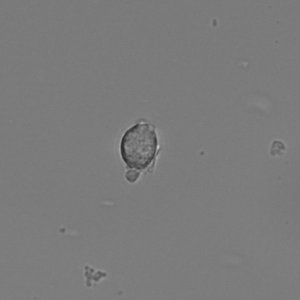

Original frames was obtained from U-118 cell line sample set. U-118 is human glyoblastoma cells widely used as model for drug testing. Also it has fibroblast like morphology and highly dynamic shape change pattern. From original microscopic images we created sets of frames containing single cell with manually outlined borders as ground truth dataset. This sets were used to have primary evaluation of segmentation successiveness. In result of described batch segmentation we obtained outline masks for each image in sequence with different accuracy of segmentation. Frames 1, 2, 9, 15, 20, 25, 40 of U-118 cell line sequence at Fig.2 an example of drastic changes of segmentation accuracy compared to manual perimeter detection.

(a) Frame 1. Cell attachment phase

Refer to caption

(b) Frame 2. Beginning of cell spreading

Figure 3: Original images of sequence is example of high dynamics of cell behavior affecting on contrast properties

The Fig.3 is representing couple of frames of sample image sequence with relatively high contrast between foreground and can be segmented with almost 95% accuracy with any method we used. Frame 1 of sample sequence presented at Fig.3(a) contain regions of hyper contrast pixels. In this case such condition does not affect on valid recognition since they are belong to object and present on margins of it and differs well from background. For Frame 2 there is absence of such pixels (Fig.3(b)) and this conditions also makes segmentation possible in relatively inflexible filtering conditions. The Frame 2 has relatively low contrast however it is seen that after filtration applied on image we achieve good difference of core and cell body compared to background as it presented at Fig.4 .